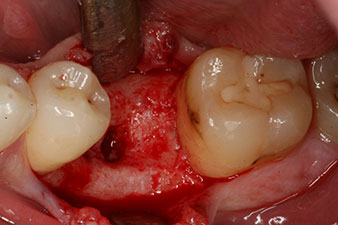

No obstante, seis semanas después de la extracción, tras la disección del colgajo mucoperióstico, se observó una osificación incompleta en el área del antiguo alvéolo mesial.

Tras la extirpación minuciosa del tejido de granulación, se incorporó el implante tal como se había planificado (blueSky, bredent).

El torque en el momento de la carga mecánica fue de 43 Ncm. Asimismo, después de atornillar un poste de medición especial adaptado al sistema de implante (SmartPeg), el valor ISQ se determinó con la sonda del módulo Osstell ISQ de W&H.